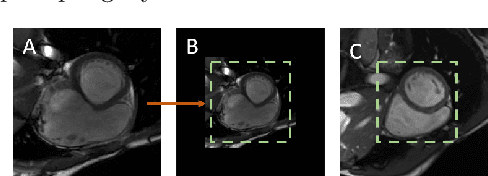

Abstract:Recently, deep networks have shown impressive performance for the segmentation of cardiac Magnetic Resonance Imaging (MRI) images. However, their achievement is proving slow to transition to widespread use in medical clinics because of robustness issues leading to low trust of clinicians to their results. Predicting run-time quality of segmentation masks can be useful to warn clinicians against poor results. Despite its importance, there are few studies on this problem. To address this gap, we propose a quality control method based on the agreement across decoders of a multi-view network, TMS-Net, measured by the cosine similarity. The network takes three view inputs resliced from the same 3D image along different axes. Different from previous multi-view networks, TMS-Net has a single encoder and three decoders, leading to better noise robustness, segmentation performance and run-time quality estimation in our experiments on the segmentation of the left atrium on STACOM 2013 and STACOM 2018 challenge datasets. We also present a way to generate poor segmentation masks by using noisy images generated with engineered noise and Rician noise to simulate undertraining, high anisotropy and poor imaging settings problems. Our run-time quality estimation method show a good classification of poor and good quality segmentation masks with an AUC reaching to 0.97 on STACOM 2018. We believe that TMS-Net and our run-time quality estimation method has a high potential to increase the thrust of clinicians to automatic image analysis tools.